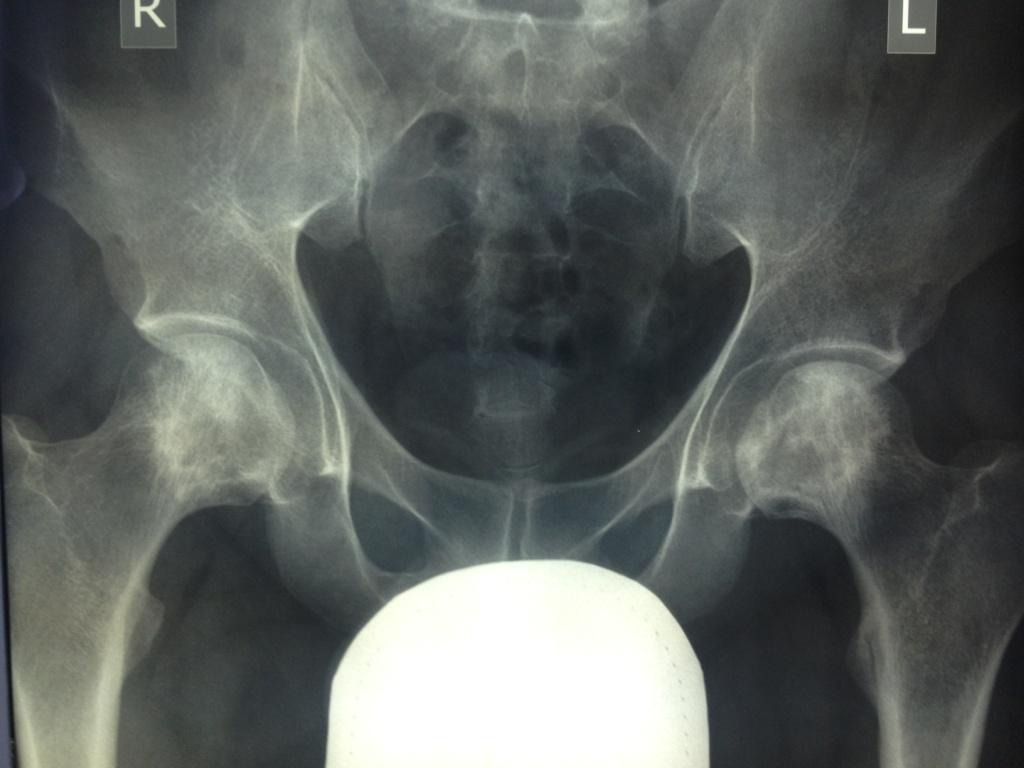

Пациента,32 лет.беспокоят боли в левом тазобедренном суставе. Болеет около 2 лет. Клинически - незначительные боли и ограничение ротации. Данные Рент, КТ, МРТ прилагаются